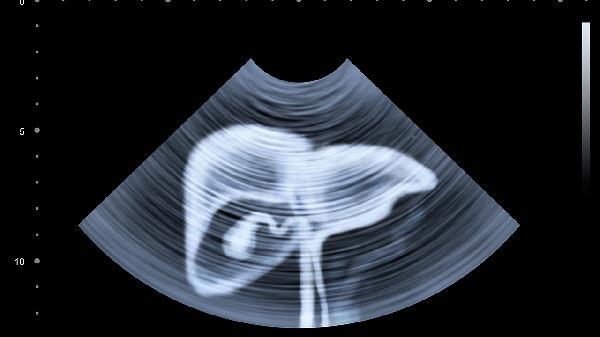

定期体检是早期发现肝脏问题的关键。通过肝功能检查、超声检查等手段,可以及时发现脂肪肝、肝炎等疾病。对于有肝脏疾病风险的人群,如肥胖、糖尿病、长期饮酒者,建议每年进行一次全面体检,以便早期干预和治疗。